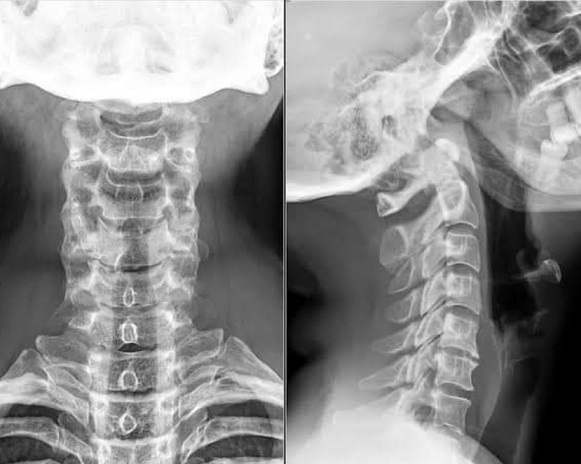

Η γνώση της ανατομίας της αυχενικής μοίρας της σπονδυλικής στήλης είναι θεμελιώδης για την κατανόηση της πάθησης. Η αυχενική μοίρα περιλαμβάνει επτά σπονδύλους και χωρίζεται σε δύο κύριες περιοχές, την άνωτερη (Α1 και Α2 σπόνδυλοι) και την κατώτερη (Α3 έως Α7 σπόνδυλοι). Ο πρώτος αυχενικός σπόνδυλος, γνωστός ως άτλαντας (Α1), υποστηρίζει το βάρος του κρανίου και επιτρέπει το νεύμα. Ο δεύτερος αυχενικός σπόνδυλος, που ονομάζεται άξονας (Α2), διαθέτει μια μοναδική οστική προβολή, τον οδόντα ,η οποία αρθρώνεται με τον άτλαντα. Αυτή η περιστροφική άρθρωση επιτρέπει την περιστροφή και την πλάγια κίνηση της κεφαλής. Οι κατώτεροι αυχενικοί σπόνδυλοι έχουν πιο τυπικά σπονδυλικά σώματα και οι λειτουργίες τους περιλαμβάνουν την παροχή σταθερότητας, ευλυγισίας και υποστήριξης στον αυχένα. Οι αυχενικές αρθρώσεις είναι τα σημεία ένωσης μεταξύ των σπονδύλων. Οι αυχενικοί δίσκοι είναι δομές που βρίσκονται ανάμεσα στους σπονδύλους και λειτουργούν ως απορροφητές κραδασμών , διευκολύνοντας την κίνηση του αυχένα. Στις δομές του αυχένα αναγνωρίζονται επίσης ο νωτιαίος μυελός, οι νωτιαίες αυχενικές ρίζες, οι αγγειακοί κλάδοι, οι σύνδεσμοι και οι υπερκείμενοι μύες.